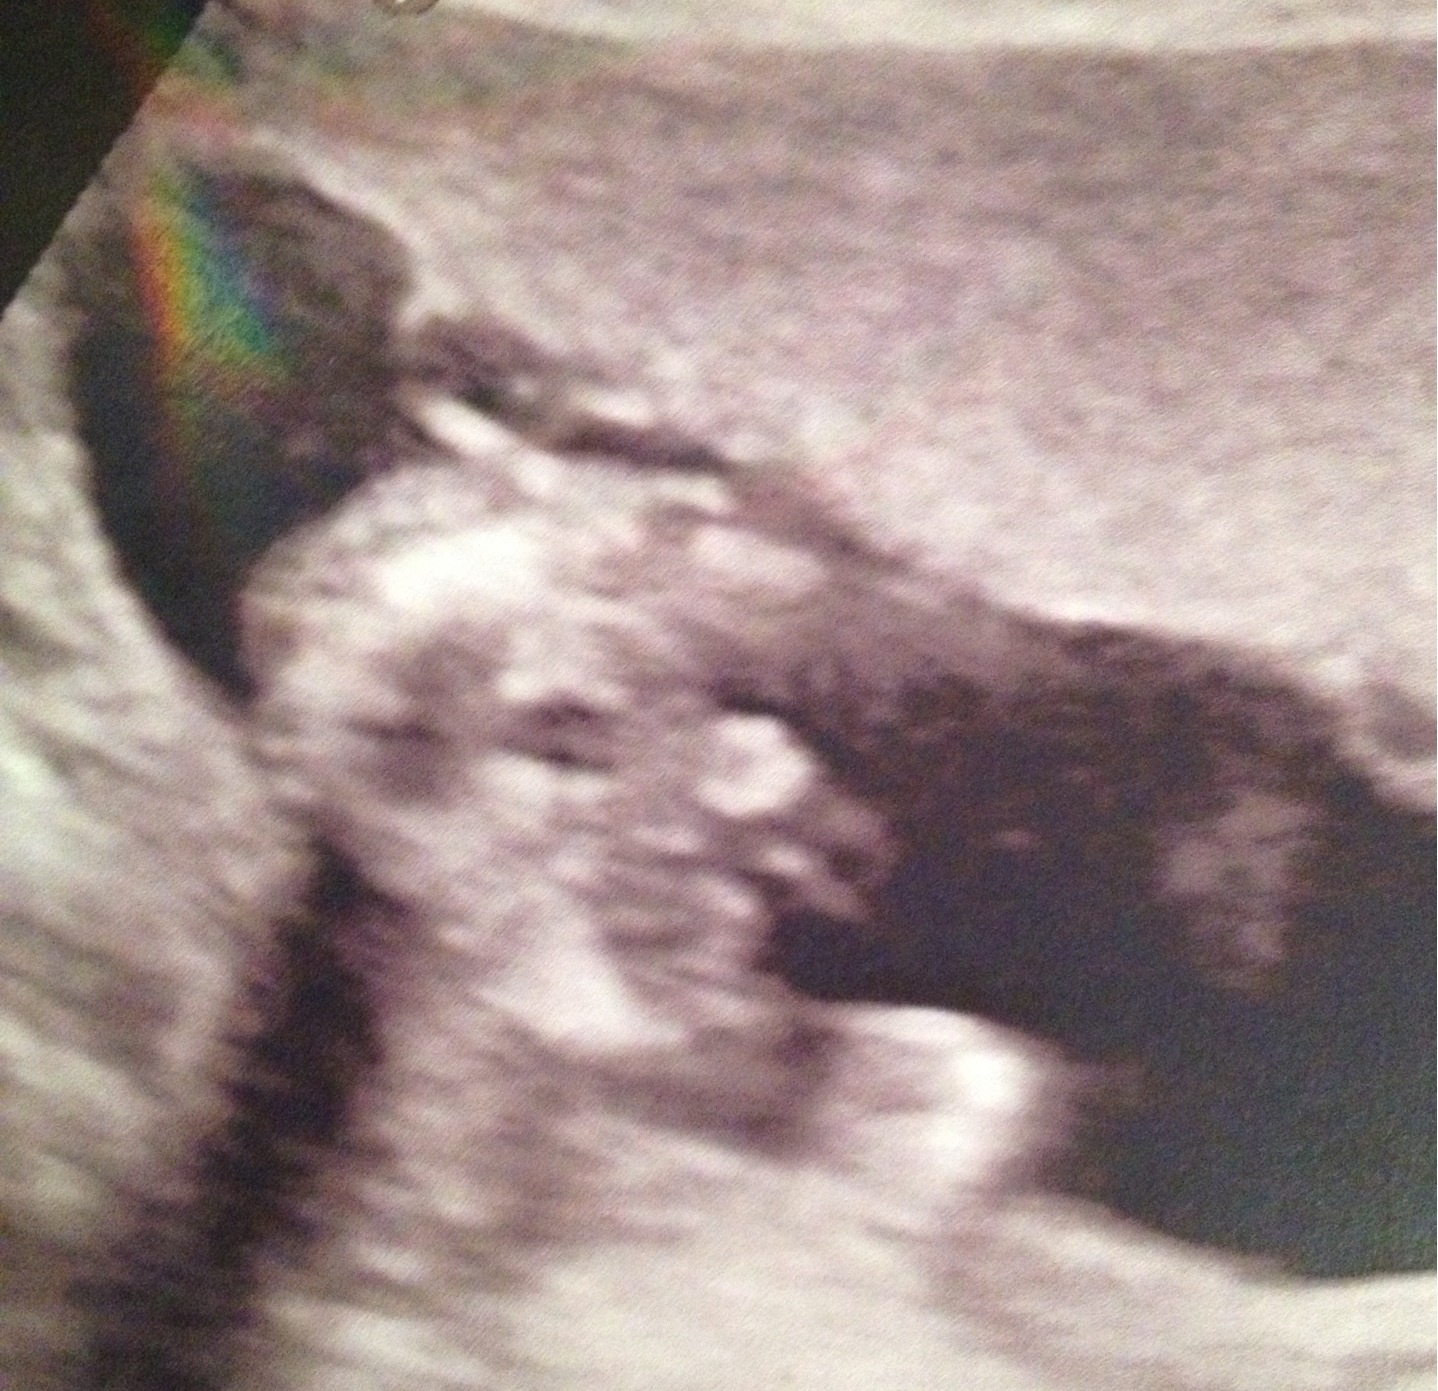

je comprends tout a fait depuis qu'on sait le sexe on a l'impression que c'est vraiment bizarre c'est notre fils on parle de lui a tout le monde c'est une vrai personne sa soulage même si les médecin ne comprennent pas toujours et des fois il le dise pas surtout pour une fille car a 13 sa surtout rien n'est sur .... La toi a ton stade si il est coopérant qu'il veut bien montrer tu le saura ... Nous il a voulu nous montrer que ses fesses et son zizi la dernière fois je vous met la photo de ses fesse et son zizi lol le rond blanc c'est ses testicules et après le zizi et le gros truc blanc c'est ses fesses lol